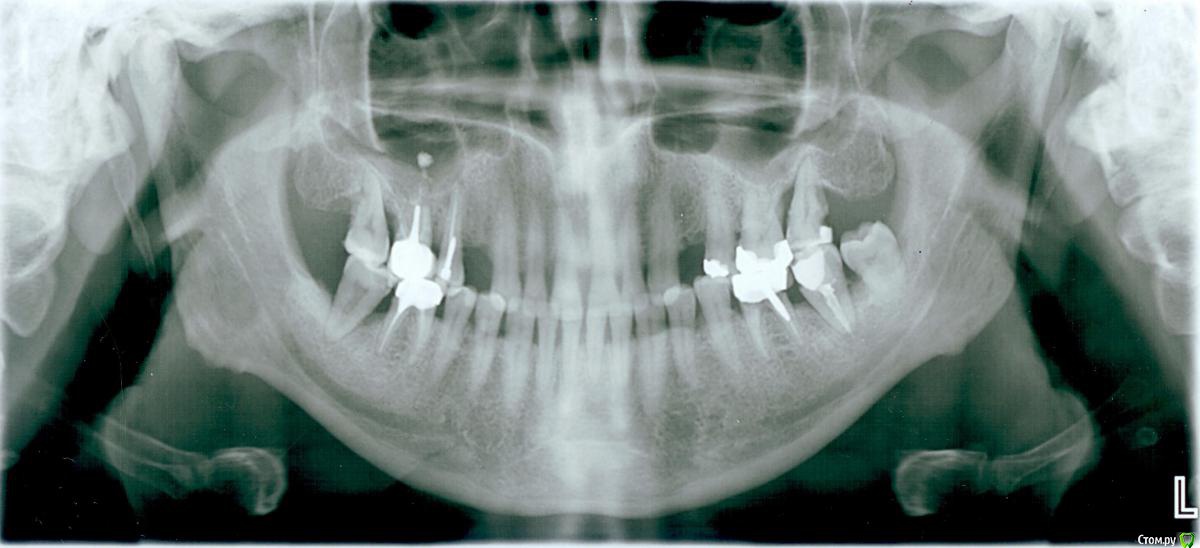

3авулон Опубликовано 31 июля, 2017 Поделиться Опубликовано 31 июля, 2017 Добрый день!Нежданно негаданно в марте месяце показал Стоматологу свою верхнюю левую семерку (стоит боком) и получил четкое указание - удалять ее (мне это не новость, гораздо интереснее было бы узнать, как на ее место поставить новый зуб) и ОБЕ нижние семерки, так как вокруг них сильное воспаление и они фактически плавают в гною. Я этого вообще не замечал ((( Шок это по нашему ((( Причем надо сказать что перед этим консультировался в нескольких клиниках (и местячковых и государственных) - на предмет установки двух имплантов верхних четверок - все готовы были установить их "хоть завтра" (и это с таким воспалением во рту?). Ну что делать, поехал удалять. Слово за слово с доктором решили таки попробовать полечить, если что потом и удалим. Парадолтолог чистила карманы, колола сыворотку из крови, я антибиотики пил... Вот теперь ждем три месяца, которые скоро заканчиваются. Параллельно бывал на осмотре у других докторов, вроде бы гноя больше не видят, но все равно говорят что эти карманы не могут не забиваться и нужно эти зубы удалять. Причин почему такое происходит никто не называет - генетика, психосоматика и т.д... А если удалять семерки - то зачем мне восьмерка и четвертая семерка? И пишут "удалить пять зубов!", оставив по шестые... упс... вот так в 45 лет... я не готов. Готов бороться, лечить, оперировать, делать что скажут, лишь бы спасти и сделать все правильно (к сожалению каких только ВЗАИМОИСКЛЮЧАЮЩИХ мнений я не наслушался) ((( Свежий снимок прилагаю. Сравнивал его с аналогичным 9 месячной давности, наложив их друг на друга - каких то изменений не вижу.... Ссылка на комментарий